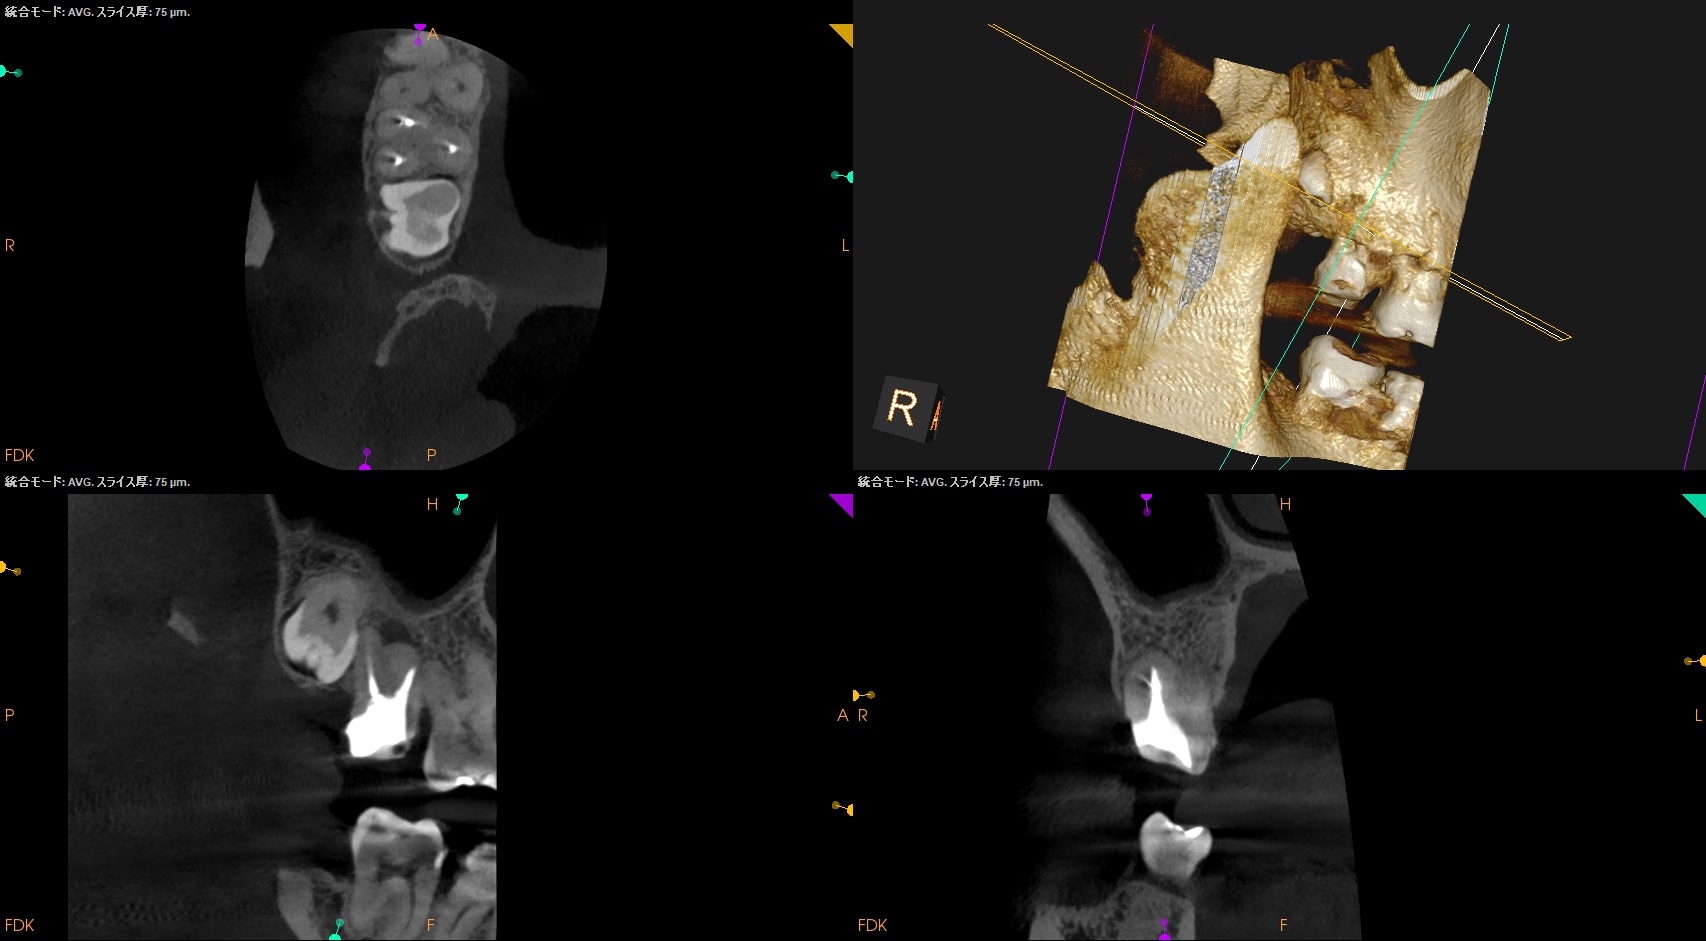

#2 Intentional Replantation(2025.12.12)

脱臼して抜歯しているので再植は難しいであろう…という印象を抱かさせるような抜歯作業だ。

抜歯窩を確認した。

ここからは口腔外作業になる。

メチレンブルーで染め出してRoot resectionした。

切断部分をメチレンブルーで染め出した後に逆根管形成した。

ファイルが破折しているMBから折れたファイルを取り出そうとするが困難であった。

仕方がないのでそのままにして逆根管形成を進めていった。

逆根管充填した。

術後にPAを撮影した。

折れたファイルはIntentional Replantationの術式では取れなかった。

が、それをあえて取ろうという考えは私にはない。

MB

DB

P

問題はないだろう。